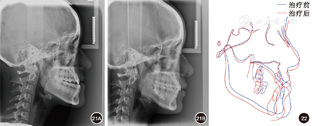

覆盖正常。全口曲面体层X线片示牙根排列基本平行。患者对早期即解决主诉感到满意,治疗前后头颅侧位X线片及头影描迹重叠图见

矫治后患者面型好,正面观患者面部对称,侧面直面型。上下颌牙列排列整齐,上前牙未发生明显唇向倾斜,下前牙去代偿。磨牙中性关系,前牙覆

覆盖正常。

过小牙修复间隙预备,维持

修复间隙。全口曲面体层X线片示牙根排列基本平行。患者对治疗早期即解决主诉感到满意,术后正畸阶段患者因妊娠而放弃前牙精细调整。